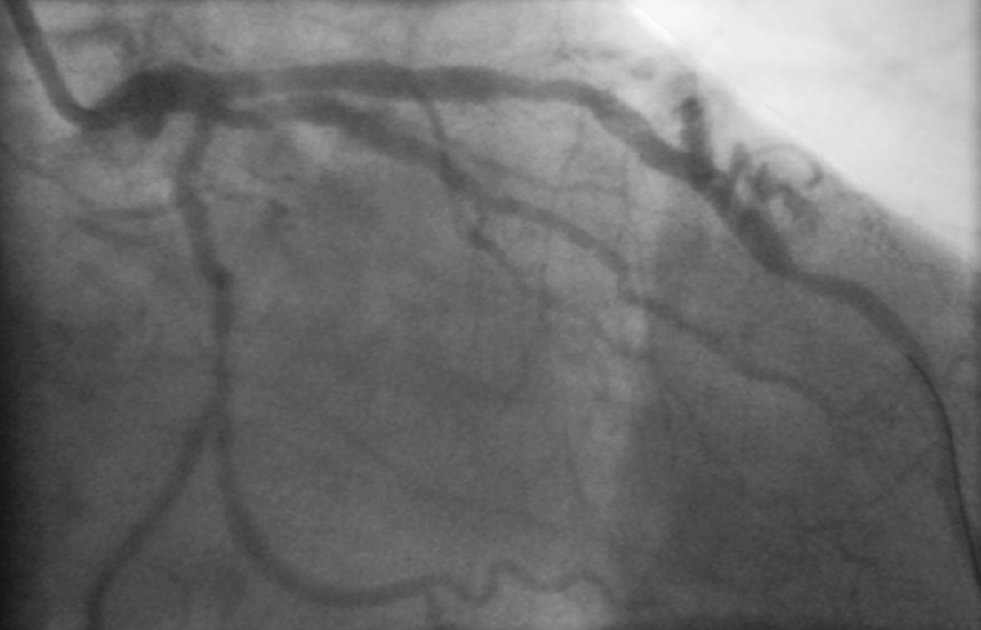

A 59-year-old male patient was admitted to the Coronary Care Unit because of a non-ST-elevation acute coronary syndrome. An early angiography showed two-vessel coronary artery disease of a large obtuse marginal branch and the left anterior descending artery with two lesions (Fig. 1 and online video). What is your diagnosis?

Fig. 1

Still image of right anterior oblique (RAO) view of the coronary angiography of our patient (see also the online video (online supplement))